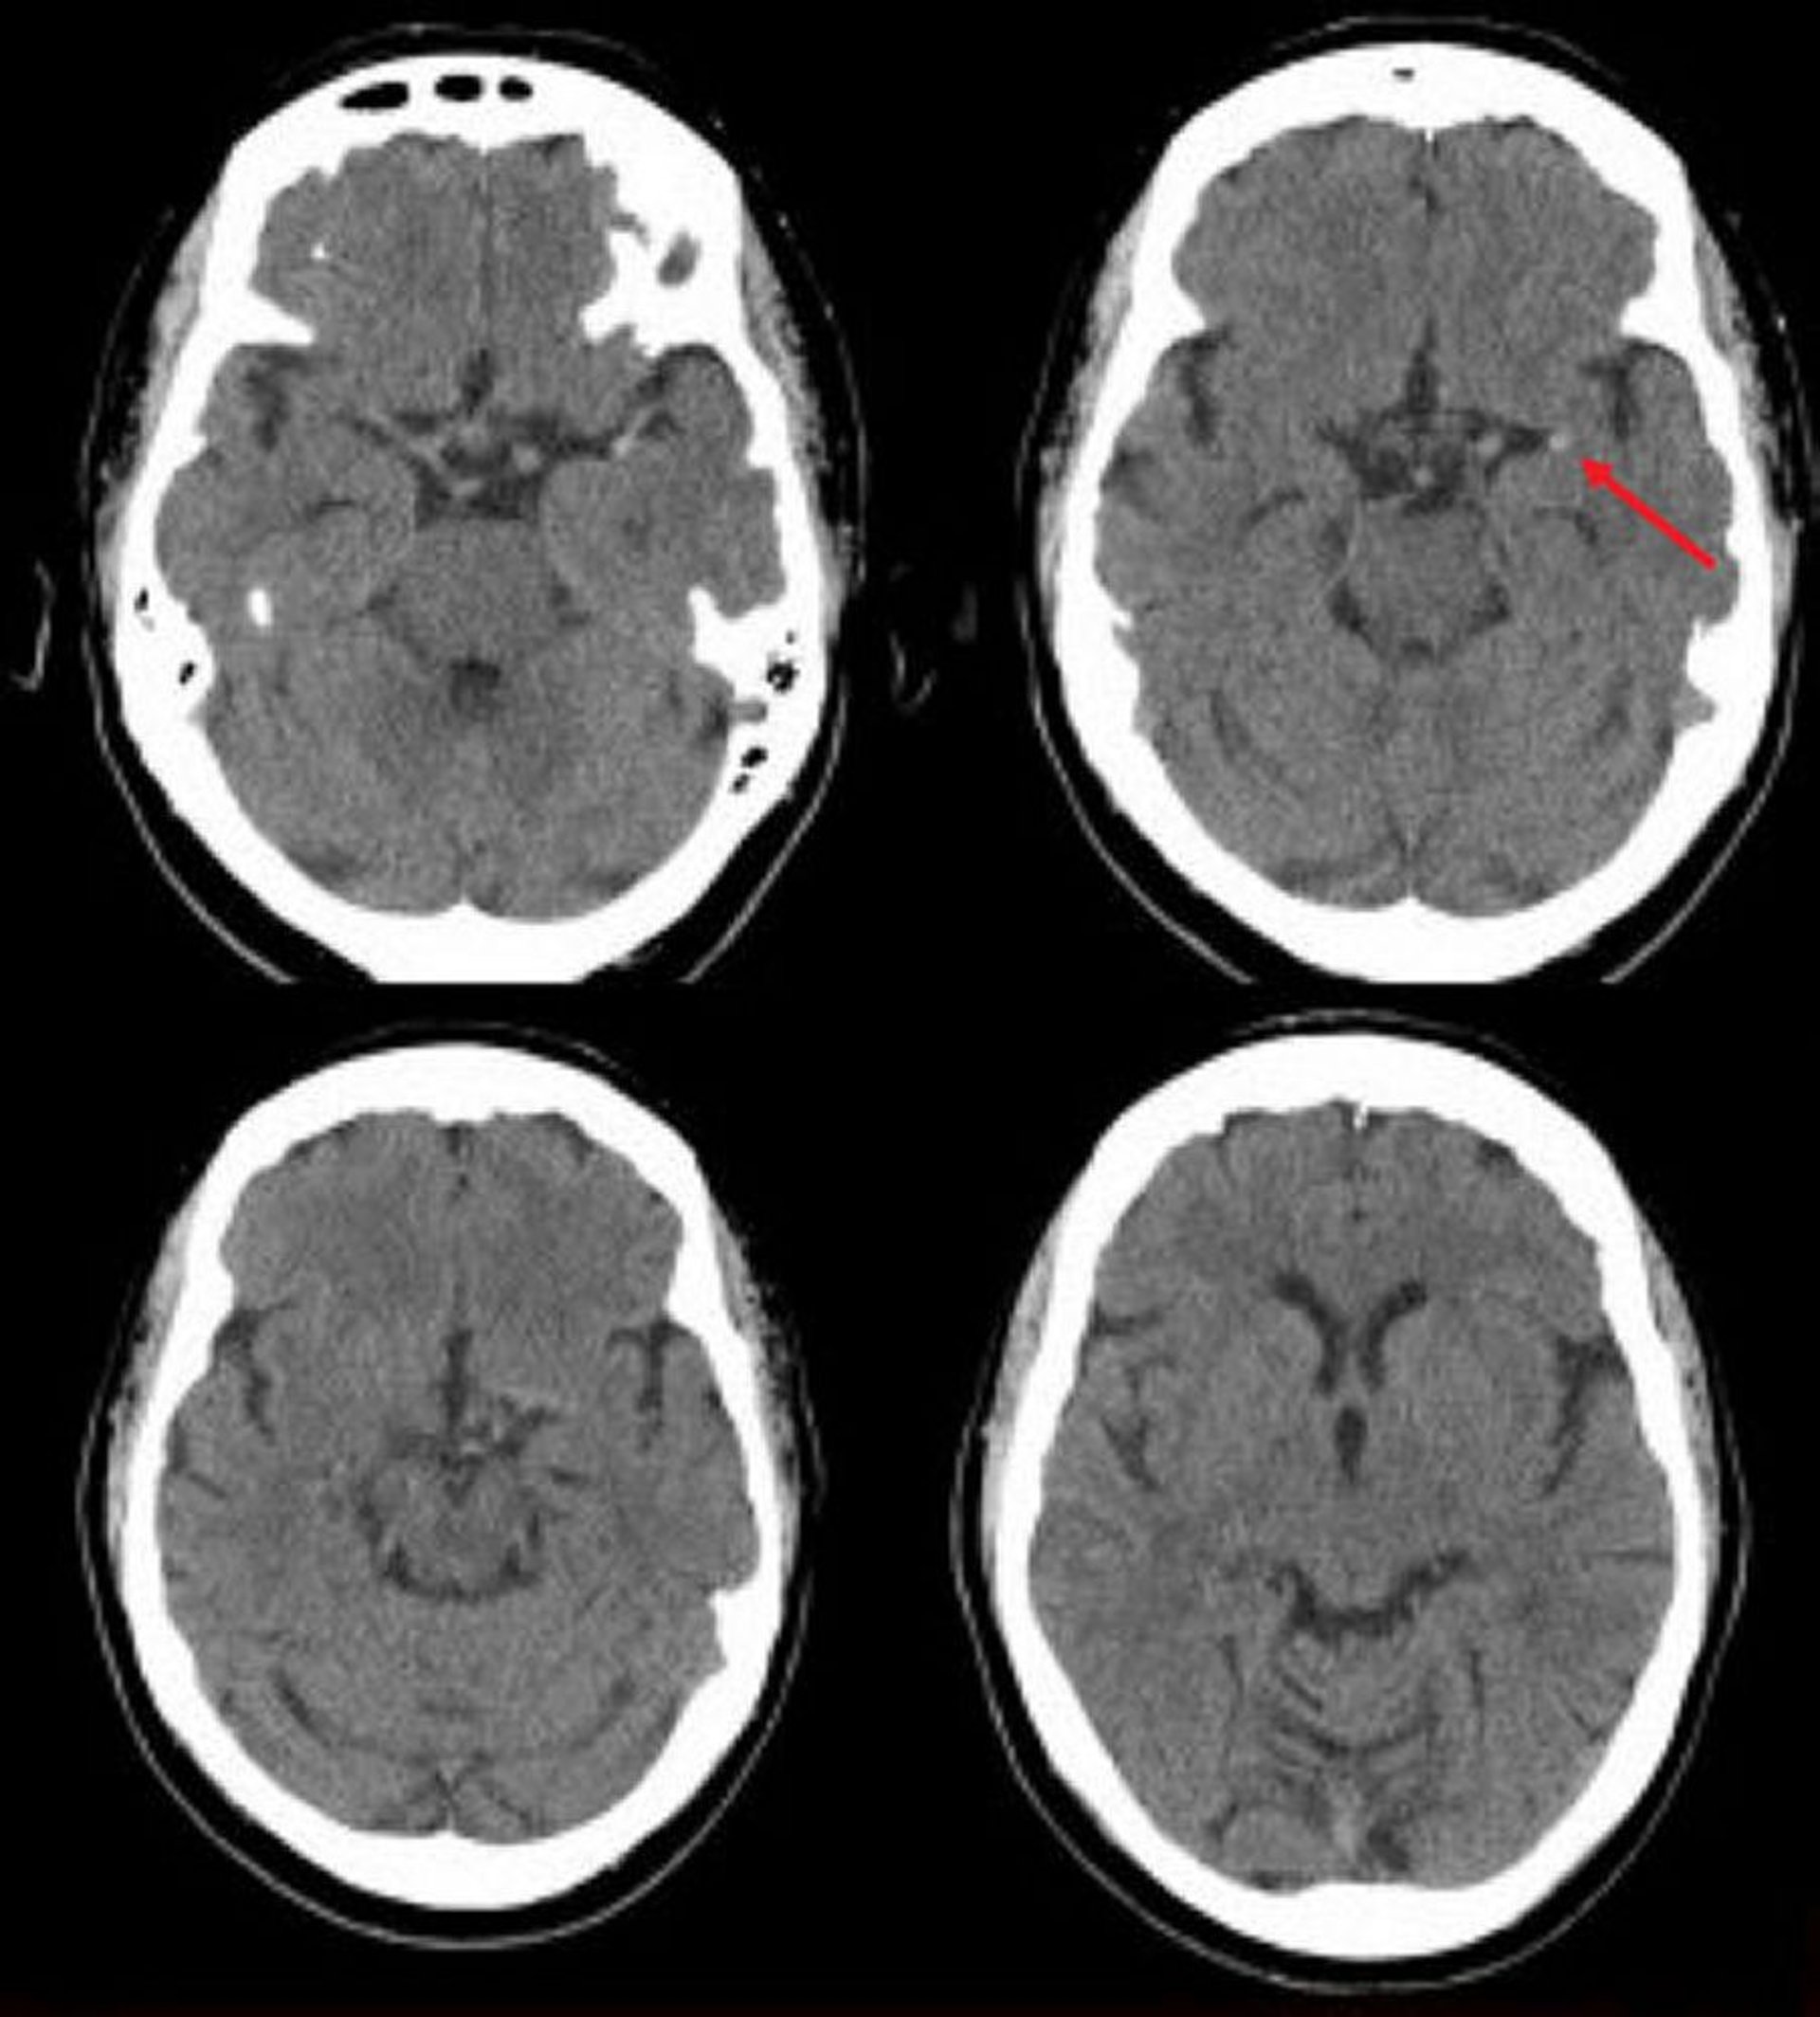

Accidente cerebrovascular isquémico en la arteria cerebral media izquierda (TC)

Esta TC de cráneo sin contraste muestra una arteria cerebral media izquierda hiperdensa. Este hallazgo indica un coágulo focal en la arteria cerebral media izquierda (flecha).

Image courtesy of Ji Y. Chong, MD.